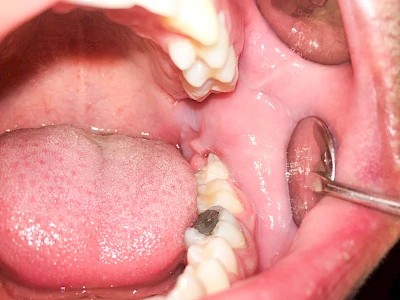

Bei einer Fistel hat sich meist eine Entzündung (manchmal auch Erreger selbst) z. B. aufgrund von Karies oder aufgrund eines Unfalls über den Zahnnerv und die Wurzelspitze (Apex) in den umliegenden Knochen ausgebreitet (apikale Parodontitis) und schnell einen Weg durch den umgebenden Knochen und die aufliegende Schleimhaut in die Mundhöhle gebahnt.

Fisteln sind in der Regel nicht schmerzhaft und fallen häufig als kleine Öffnung weiter entfernt vom Zahnfleisch nahe der Umschlagfalte auf. Aus der Fistelöffnung entleert sich spontan gelbliches Sekret (Eiter) oder es lässt sich mit dem Finger ausstreichen. Manchmal beschreiben die betroffenen Menschen immer wieder einen komischen Geschmack im Mund.

Im fortgeschrittenen Stadium kann die Schleimhaut sich weiter zurückgezogen haben und die Wurzelspitze sichtbar sein. In der Regel treten bei Fisteln keine Schwellungen auf, weil sich die Entzündung nicht im Gewebe ausbreitet.